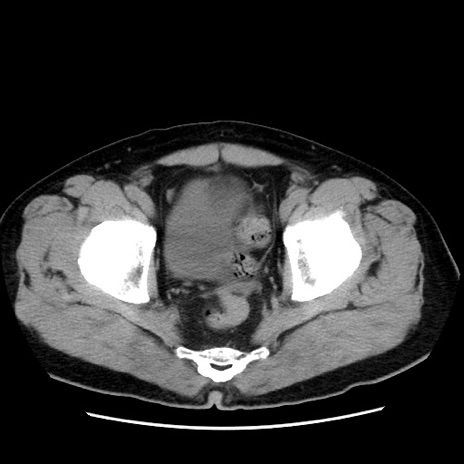

症例16(横断像)

【症例】 70歳代男性

【主訴】 腹痛、嘔吐

【現病歴】 約1ヶ月前より間欠的に腹痛と嘔吐あり、当院消化器内科を受診したところCTで多発する肝臓のLDAを指摘され、精査中であった。以降は消化器症状は安定していたが、2日前より嘔気と腹痛があり、同日より排便・排ガスが消失した。改善認めず、 本日、救急外来を受診した。

【既往歴】 大腸ポリープ切除後。

【身体所見】意識清明・会話良好、BT 36.3℃、BP 127/80mmHg、 P 80bpm、腹部:膨満あり、平坦・軟、上腹部正中および下腹部正中に圧痛あり、反跳痛なし、筋性防御なし。

【データ】WBC 7200、CRP 0.77